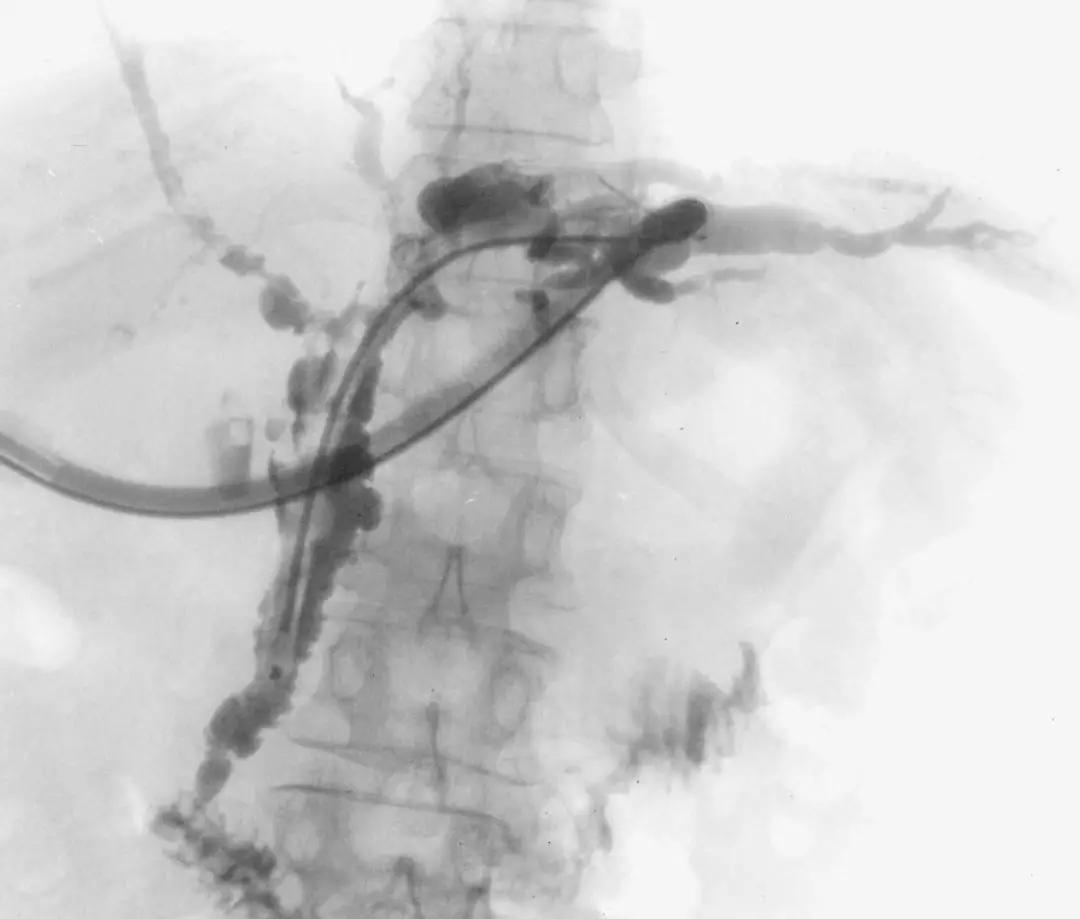

A.胆道影像学检查

ERCP:胆管狭窄与扩张交互,呈串珠状改变

多发短小狭窄,胆管环状受累

PTCD:胆管呈边缘不整羽毛状

ERC:胆管壁呈憩室样突出